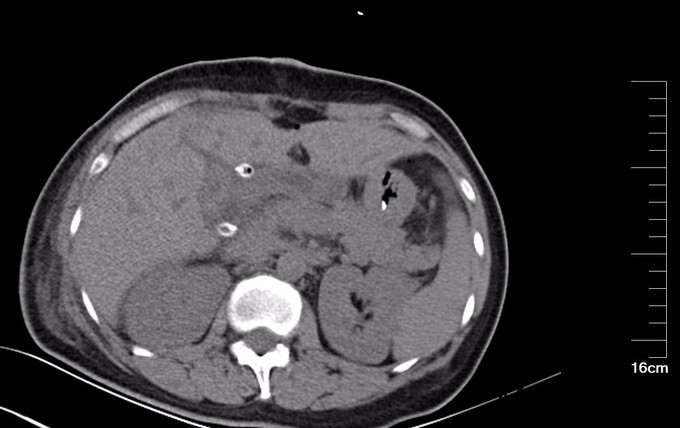

查体:腹部略膨隆,未见胃肠型及蠕动波,未见腹壁曲张静脉,右上腹部压痛阳性,无反跳痛或肌紧张,未及包块,肝脾肋下未及,Murphy氏征阳性,肝区扣痛阳性,肾区无扣痛,肠鸣音减弱,约4次/分,未闻及气过水声。 辅查: MR平扫+增强:肝脏大小形态未见异常,各叶比例正常,未见异常信号灶。肝内胆管、胆囊管及胆总管多发囊状扩张,胆总管直径6cm左右,壁厚且明显强化,腔内点状T2WI低信号影。胆囊饱满,其内可见聚集点状低信号影,胆囊壁增厚且明显强化。门脉血管显示清楚,走行正常。胰腺形态信号未见异常,胰管未见扩张。脾脏不大。增强扫描未见异常强化病灶。 MRCP:胆囊体积增大,肝内胆管、胆囊管及胆总管多发囊状扩张。胰管显影,形态走行未见异常。 CT 胆总管囊状扩张,囊壁较厚,前壁见点状钙化,较宽处直径约6.7cm,胆总管末端壁增厚,管腔狭窄;增强扫描扩张胆总管壁明显强化。肝内胆管扩张,胆囊增大,胆囊壁增厚、强化尚均匀,囊内未见异常密度影。 肝内未见异常密度影。胰腺形态、密度未见异常。脾不大。腹膜后未见确切肿大淋巴结影。

诊断: 胆总管囊肿 治疗:全麻下手术治疗。术中探查,见胆囊大10x6x4cm,肝门部可触及肿大胆总管,直径约6cm,向下延续到胰腺段,切除胆囊,于肝总管横断,向下剥离胆总管,直至胰腺段,仔细分离胆总管与胰腺,避免胰腺组织破碎,直到胆总管变细部位,切断之,远端缝扎,继续行肝管空肠Roux-en-Y吻合术。术后病理胆总管绒毛管状腺瘤,伴高级别上皮内瘤变,有恶变趋势,慢性胆囊炎。

术后检测引流液淀粉酶,术后第一天引流液淀粉酶583U/L, 按照血淀粉酶正常值3倍定义胰瘘,存在胰瘘,术后第4日272 U/L,术后7日118 U/L,已经正常。复查腹部CT, 上腹壁见手术瘢痕影,腹壁下见少量渗出、积气;肝内胆管仍扩张、程度较前减轻,胆囊未见显示,胆囊窝留置导管、局部积气。胆总管囊肿病因不清,对此假说繁多,大多数病例被认为是先天性发育不良所致。胆管壁薄弱有认为管壁的支撑组织存在先天性缺损或存在异位胰腺组织使管壁处于低张状态;胆总管远端梗阻,致管内压力增加从而引起扩张。 分为三型:普通型,憩室型,十二指肠内胆总管膨出,本病例属于普通型。临床表现为间歇性上腹痛、右上腹肿块和黄疸,称为胆总管囊肿三联征,本病例无黄疸。一旦作出诊断,即应采取手术治疗,内引流为宜。胆总管囊肿不手术,会继发结石,并且恶变,本病例经过病理证实已经出现恶变倾向,早期尽快明确诊断,及时手术治疗是此病预防的关键。